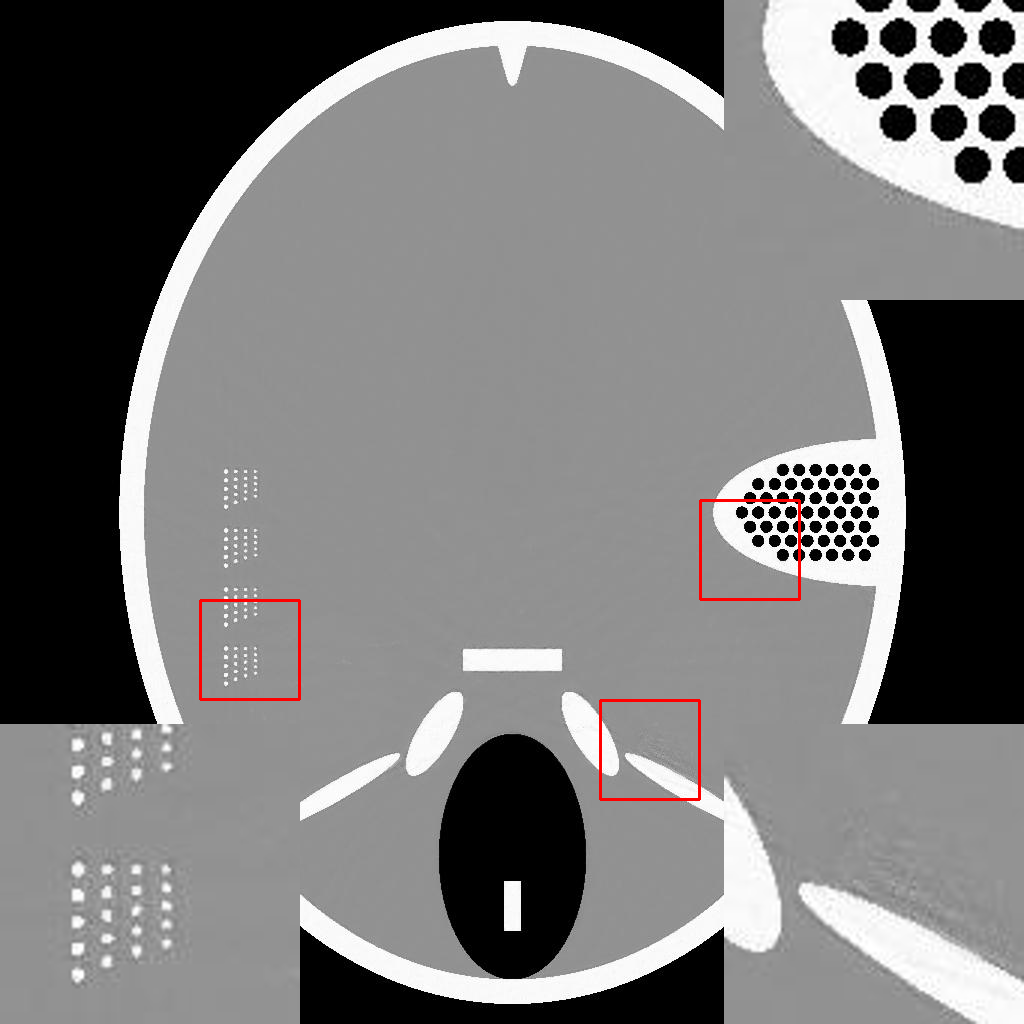

To demonstrate the efficacy of the RBP connection and show the details of the RBP-DIP’s reconstruction process, the procedure of a limited-angle CT reconstruction is shown in Fig.2. Its first row illustrates the results of reconstruction across different iterations, whereas the second row presents the respective inputs fed into the U-net, which are updated through the RBP connection. Here, the number of views is set to , uniformly distributed from to . This scenario presents a challenging limited-angle CT reconstruction problem.

In the first iteration, as depicted in Fig.2a, the input image undergoes an update via the RBP connection prior to being fed to the U-net. Thus, this input is the normalized first iteration output of the implemented IR algorithm (normalized back projection image in our case). The output appears completely randomized since the entire neural network is randomly initialized.

In the 10th and 20th iterations (Fig.2b and Fig.2c), the DIP property effectively expedites the recovery of the object over its support. Of note are lack of artifacts commonly caused by having missing views in the data. The input images highlight the region which can be relatively accurately reconstructed by conventional IR methods. This can be used to guide the model in the later iteration. In our experiment, the model capitalizes on the input images more when reconstructing the upper-left and lower-right segments of the image, while relying predominantly on the DIP property for the reconstruction of the upper-right and lower-left parts.

In the 2000th iteration, as depicted in Fig.2d, the reconstruction result becomes relatively artifact-free. At this stage, the network input primarily emphasizes the edges to help the method improve the supporting area. Moreover, the RBP connection can rectify artifacts specific to convolutional neural networks. Evidence of this can be observed in the second row of Fig.2c, Fig.2d, and Fig.2e, which display distinct horizontal and vertical patterns. These patterns are mainly caused by the convolution operation in the U-net. In other words, the DIP and RBP parts of the proposed framework are able to mutually rectify each other’s errors. Consequently, a high-quality reconstruction result is attainable, as shown in Fig.2e.